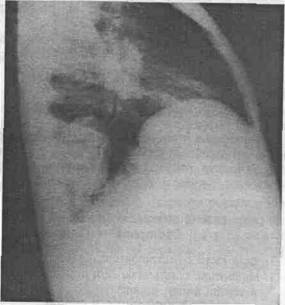

9. Tn chistui hidatic complicat examenul radiologic este caracteristic:

a. Tn stadiul de preruptura imaginea de semiluna la polul superior al opacitatii, iar clinic concomitent cu tuse si spute hemoptoice;

b. Tn eel evacuat: cavitatea intraparenchima-toasa bine delimitata cu semnul membranei ondu-late pe fundul lojei chistice (fig. 3, 4, 5).

Fig. 4 - Acelasi caz radiografie de profil, chist evacuat localizat

Fig. 3 - Radiografie fata, imagine de chist hidatic evacuat.